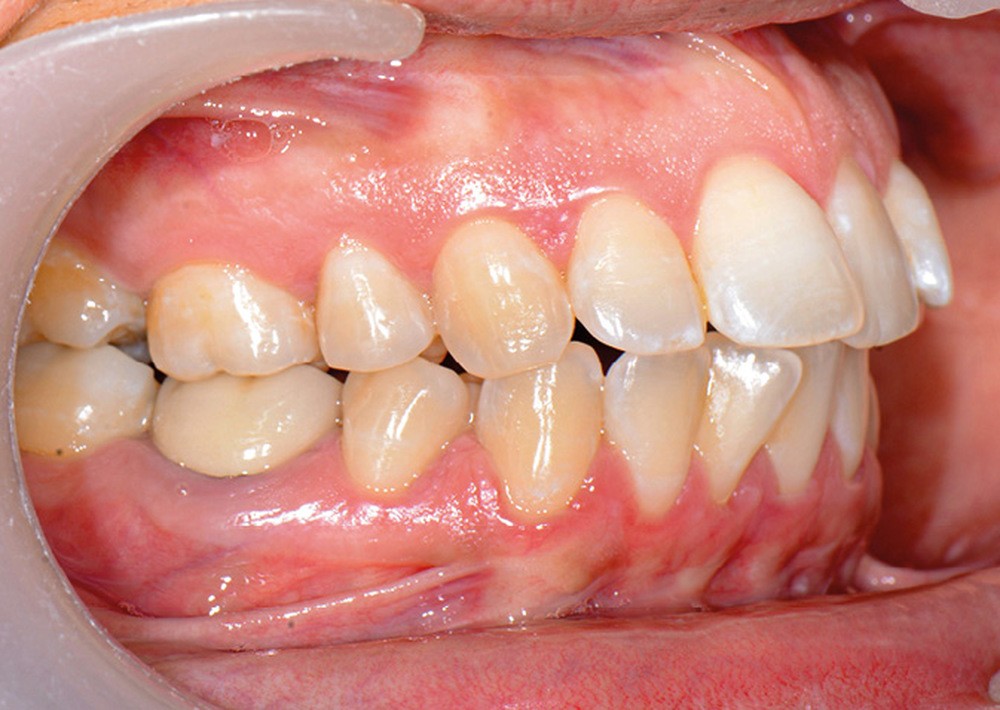

C’est précisément le cas de cette patiente de 33 ans qui présente une classe II squelettique par rétrognathie mandibulaire sur un schéma vertical hyperdivergent associée à une classe II/1 dentaire avec DDA par excès et biproalvéolie. Son profil est convexe, cis-frontal et, sur le plan fonctionnel, on peut observer une dysfonction linguale et une incompétence labiale au repos. Il en résulte une contracture des muscles de la sphère péri-orale lèvres jointes. La formule dentaire n’est pas complète puisque les quatre deuxièmes prémolaires ont été extraites lors d’un premier traitement orthodontique et qu’il y a également agénésie des troisièmes molaires 18 et 38 (fig 1 à 11).